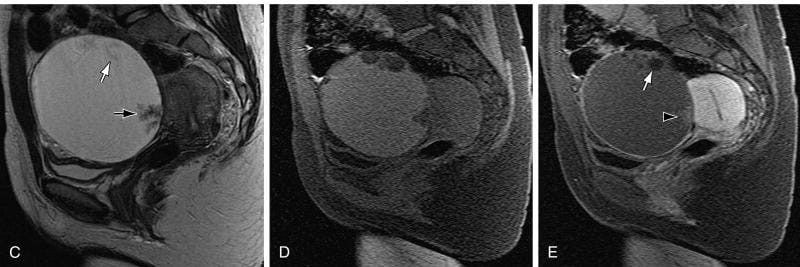

وقال الدكتور تامر مدكور، وكيل وزارة الصحة بالدقهلية، إن المريضة حضرت إلى عيادة جراحة الأورام وهي تعاني من آلام مستمرة بمنطقة الحوض، مع وجود تاريخ مرضي تضمن استئصالًا جزئيًا للرحم، وجراحة سابقة لاستئصال كيس على المبيض. وبناءً على الفحوصات والأشعة، تبيّن وجود كيس بحجم 10 سم في منتصف الحوض.